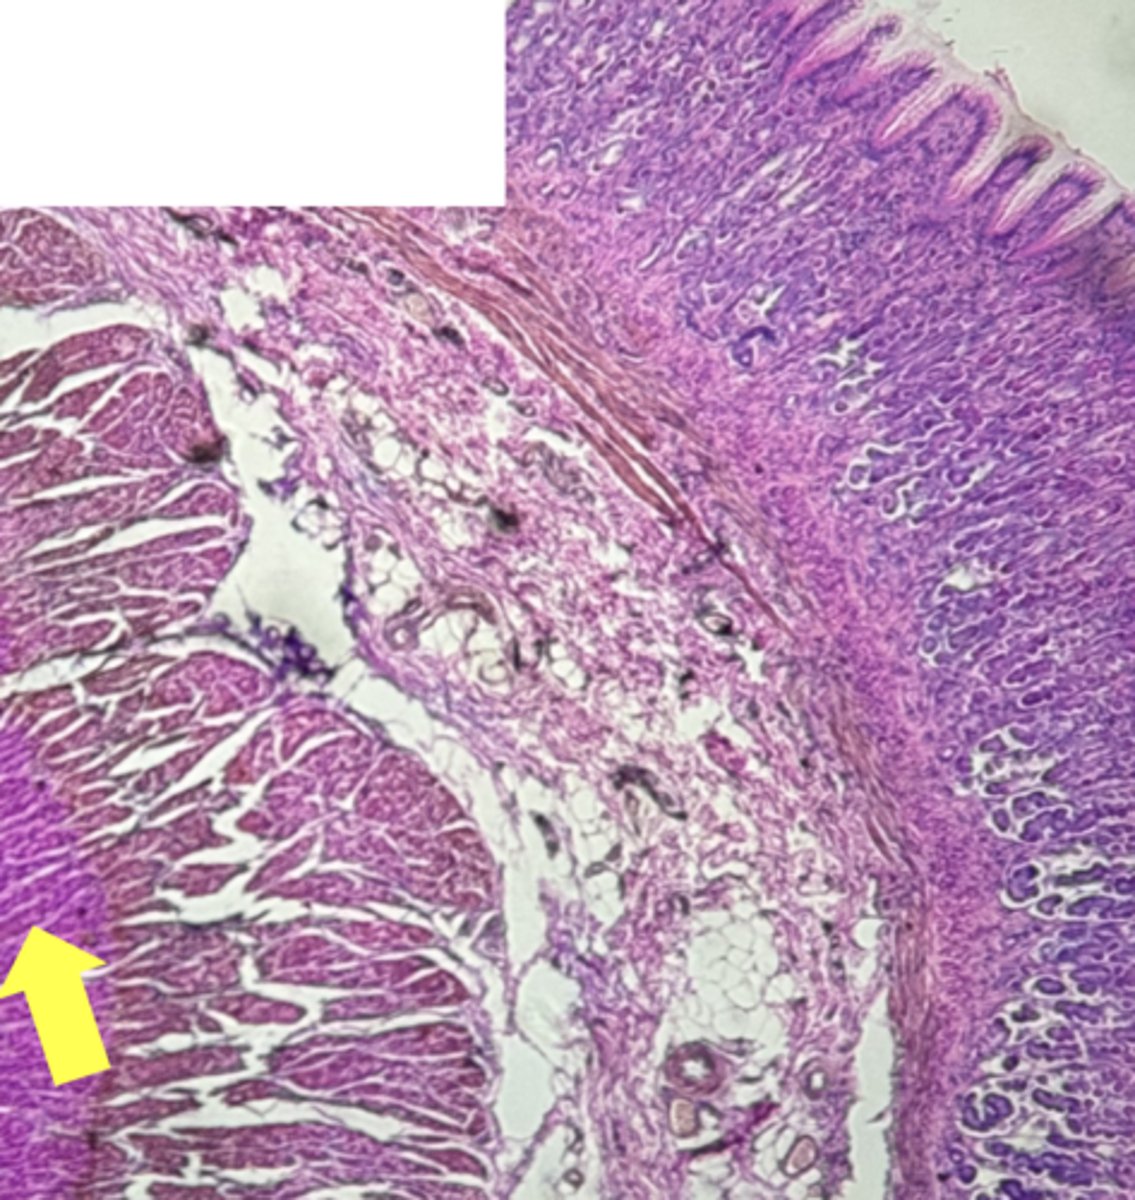

A- Esophagus

B- Stomach

Name the Tissue A & B

stomach

name the tissue

mucosa

(stomach)

submucosa

muscularis externa (3 LAYERS-KEY CHARACTERISTIC)

oblique layer

circular layer

longitudinal layer

simple columnar epithelium

gastric pits (KEY CHARACTERISTIC)

gastric glands (KEY CHARACTERISTIC)

Parietal cells- HCl (hydrochloric acid)

name the cell & what it secretes

Chief Cells- pepsinogen/pepsin

Lamina propria

muscularis mucosae

Esophagus

(esophagus)

muscularis externa

stratified squamous epithilium (KEY CHARACTERISTIC)